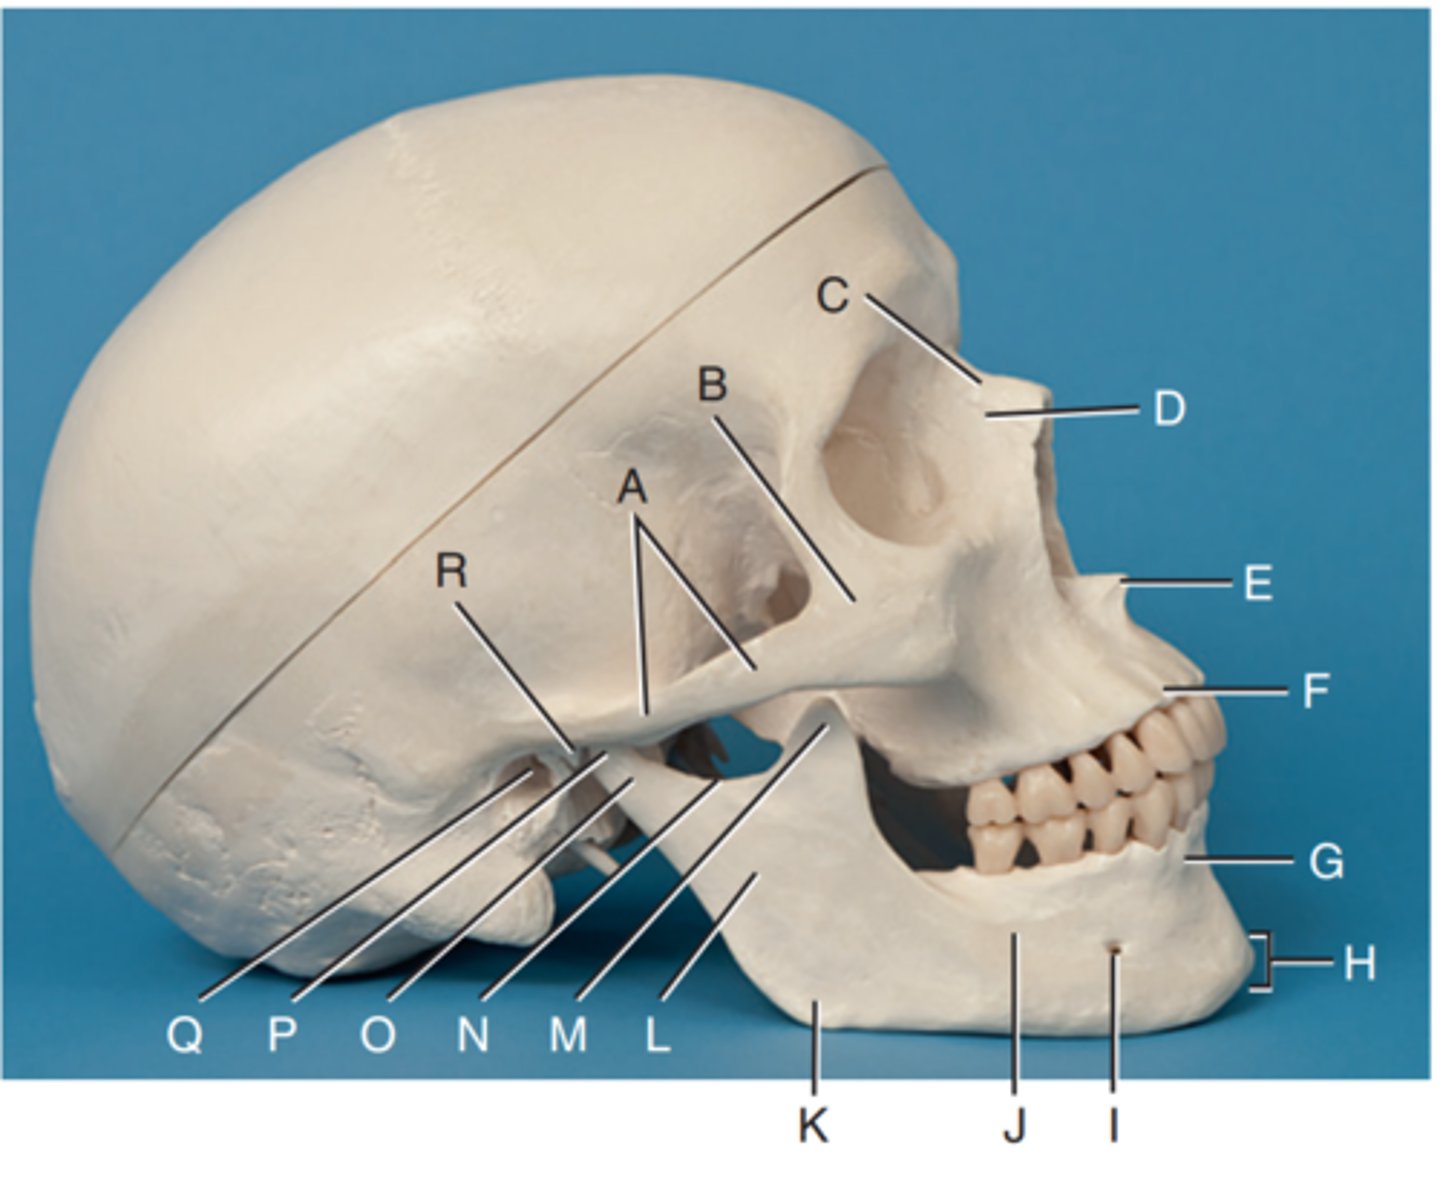

Zygomatic arch

Label A

Right zygomatic bone

Label B

Right nasal bone

Label C

Frontal process of right maxilla

Label D

Anterior nasal spine

Label E

Alveolar process of maxilla

Label F

Alveolar process of mandible

Label G

Mentum or mental protuberance

Label H

Mental foramen

Label I

Body of mandible

Label J

Angle (gonion)

Label K

Ramus of mandible

Label L

Coronoid process

Label M

Mandibular notch

Label N

Neck of mandibular condyle

Label o

Condyle or head of mandible

Label P

EAM

Label Q

TM fossa of temporal bone

Label R

Greater wings of sphenoid

Label S

Lesser wings of sphenoid with anterior clinoid processes

Label T

Ethmoid sinuses between orbits

Label U

Body of maxilla containing maxillary sunuses

Label V